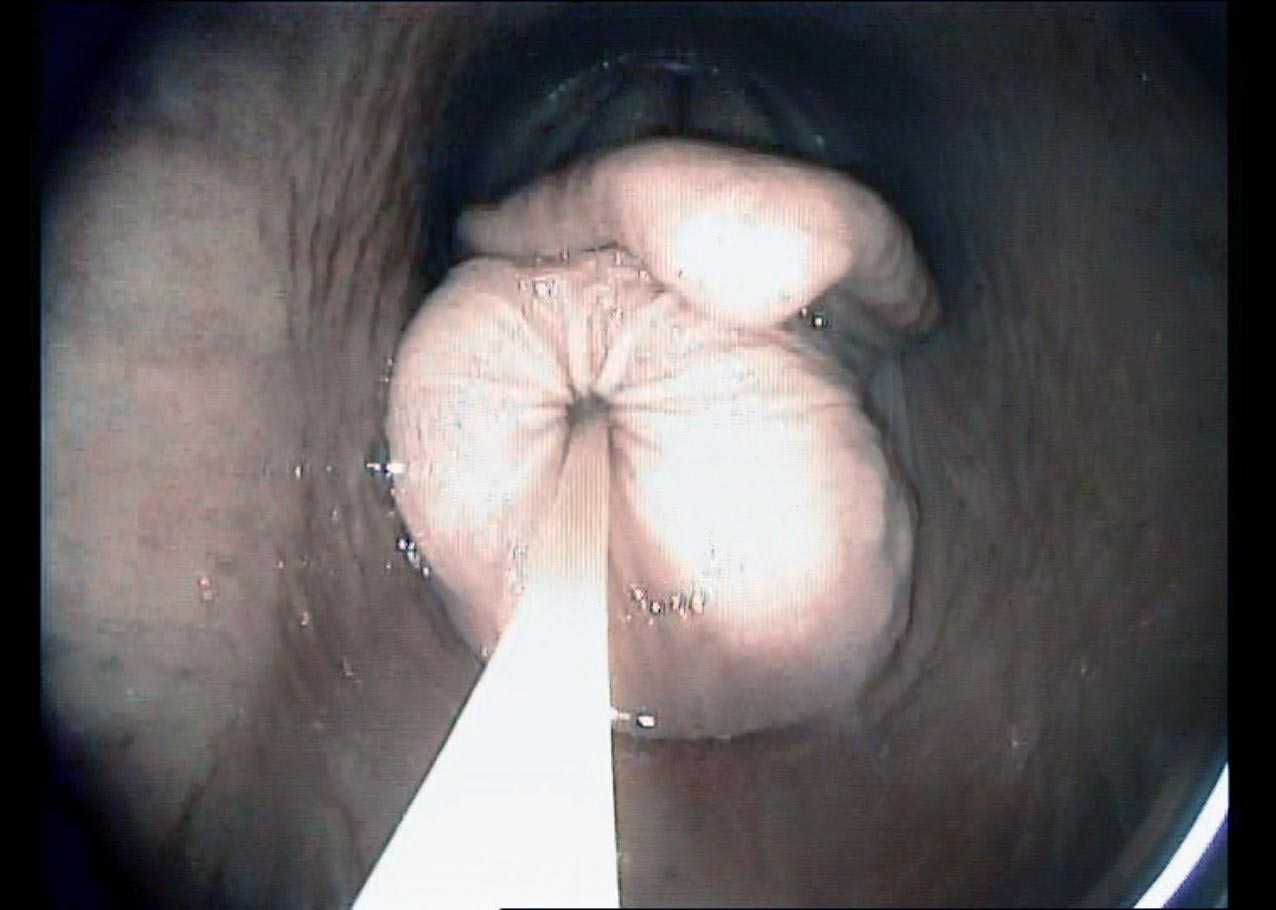

Figure 1. A videoendoscopic image demonstrating the large subepiglottic cyst at presentation. Note the secondary elevation of the epiglottis.

In this case, endoscopy of the upper respiratory tract was elected as the primary diagnostic procedure. This demonstrated a large (approximately 3cm diameter) well demarcated, mucosa-covered mass positioned ventral to the epiglottis and the epiglottic cartilage was dorsally deviated by the mass (Figure 1). A diagnosis of subepiglottic cyst was therefore made. Endoscopy of the trachea showed a small amount of food material on the tracheal walls. No abnormal respiratory secretions could be seen emanating from the sinus drainage angle on the left side.

Endoscopy of the upper respiratory tract typically confirms the presence of the cyst, although the cyst may be intermittently positioned ventral to the soft palate, making observation more challenging (Aitken and Parente, 2011).

The epiglottis is often elevated dorsally and further abnormalities, including epiglottic entrapment, may be present (Salz et al, 2013). Some cases of subepiglottic granuloma, may appear similar to a cyst (Fulton et al, 2012).